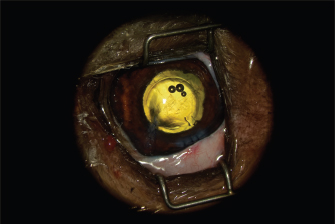

The AC was stabilized by intracameral injection of a viscoelastic gel (hyaluronic acid 1.6%, Ophteis Bio) by a perforating keratotomy port at 12 o’clock. As the base of the claw was crenelated, it was not possible to remove it through the site of penetration, which is why another perforating keratotomy port was made at 10 o’clock. The claw was grasped with Bonn’s pliers and then gently removed. The entry point of the claw and the 10 o’clock port were sutured by single stitches using polyglactin 9/0 (Vicryl 9/0). The pupil was then dilated by injection of 1 ml of epinephrine at a concentration of 1 mg/ml into the AC. The anterior lens was ruptured, and a heterogeneous traumatic cataract had already developed (Fig. 2). The lens was, therefore, removed by phacoemulsification via the port at 12 o’clock. After removal of the masses by irrigation/aspiration, the tear of the anterior capsule was shaped before injection of an implant (PFI 4X, Medicontur). The keratotomy port at 12 o’clock was sutured by three single stitches with Vicryl 9/0 after the removal of residual viscoelastic material by suction irrigation. At this stage of the surgery, a tear of the endothelium and Descemet membrane was visible, following the most likely trajectory of the claw into the AC (Fig. 3). Water bubbles were already forming in the corneal stroma. An injection of 0.25 μg of tissue plasminogen activator (Actilyse®, BOEHRINGER INGELHEIM) was performed in the AC at the end of the intervention to limit postoperative fibrinous collection. The claw was sent to the laboratory for bacteriological analysis.

Fig. 3. Appearance of the eye after implantation. The endothelium and Descemet membrane are torn, which causes early formation of water compartments in the corneal stroma.